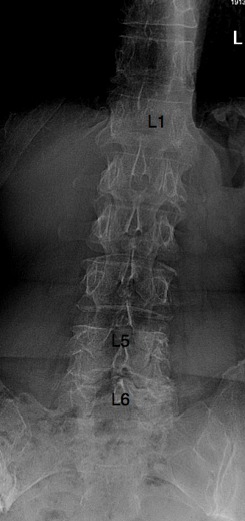

There are six lumbar vertebrae (normally five). The body of L5 has moved anterior on L6, owing to degeneration of the facet joints. There is no spondylolysis (pars fracture). Also degenerative facets at L6-S1.

The lumbar lordosis has greatly increased. A list of the spine (and possbibly the pelvis) to the left is seen. (no specific mention whether the X-rays were taken erect or not).